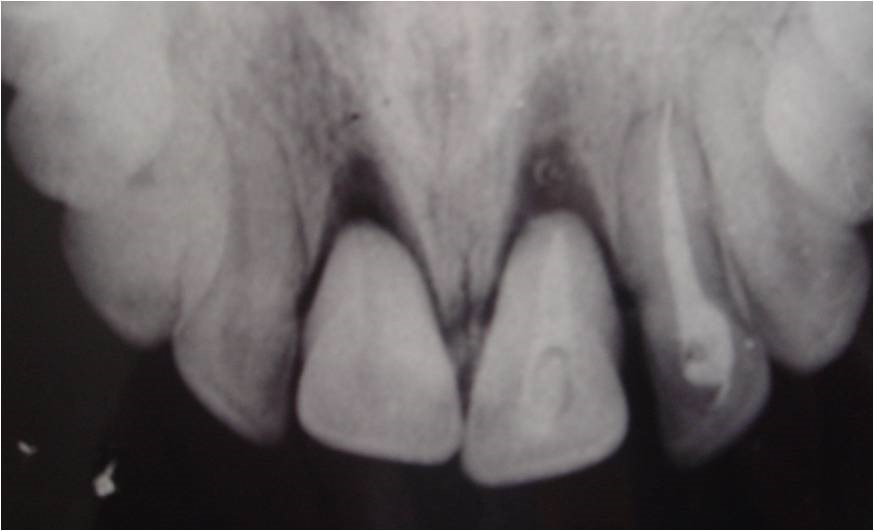

2305. На рентгенограмме у пациента с травмой челюстно-лицевой области дифференцируется ______ зубов